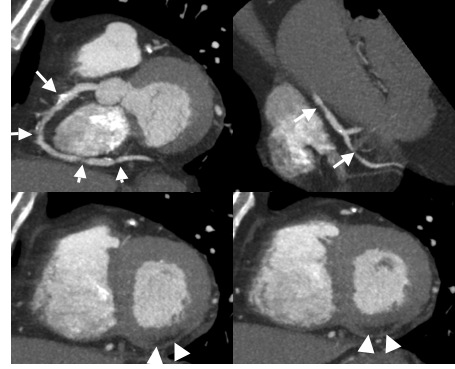

72y, m, laut EKG St.p. nicht-rezentem MCI (Hinterwand)

Zuweisung zur CTA zum KHK-Nachweis bzw. zur Therapieplanung

Darstellung zahlreicher relevant stenosierender, teilweise verkalkter Läsionen im Verlauf der RCA (Pfeile). Passend zum EKG-Befund sowie zu den Läsionen im Verlauf der RCA ausgedehnte Narbe im Bereich der Hinterwand (Pfeilspitzen).